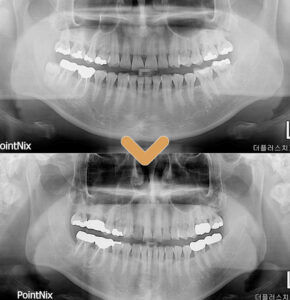

발치 후 사진을 보시면 잔존 치근 없이

깔끔히 발치가 된 모습을 볼 수 있으며,

마취가 풀린 후에도 신경 손상 없이

감각이 돌아왔다고 하셨습니다.